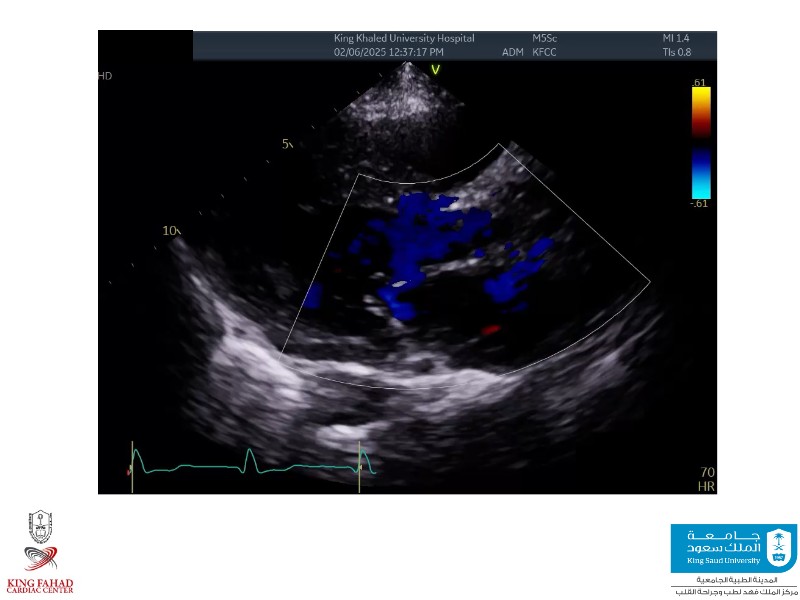

This session helps you anticipate and address complex scenarios such as mitral valve-in-valve, TAV-in-SAV, and valve-in-valve-in-valve procedures. Learn from expert case discussions that explore procedural strategies, technical challenges, and best practices to optimize outcomes in redo structural heart interventions.

- To anticipate and manage second valve scenarios with SAPIEN 3 Ultra RESILIA, including mitral valve-in-valve, TAV-in-SAV, and TAV-in-TAV